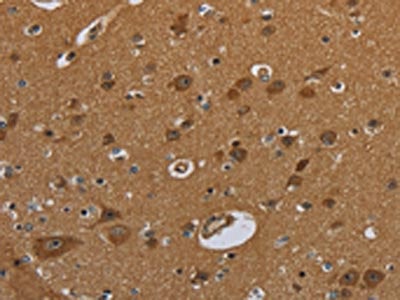

IHC (Immunohiostchemistry)

(The image on the left is immunohistochemistry of paraffin-embedded Human brain tissue using AAA238958(NR3C1 Antibody) at dilution 1/30, on the right is treated with fusion protein. (Original magnification: ×200))